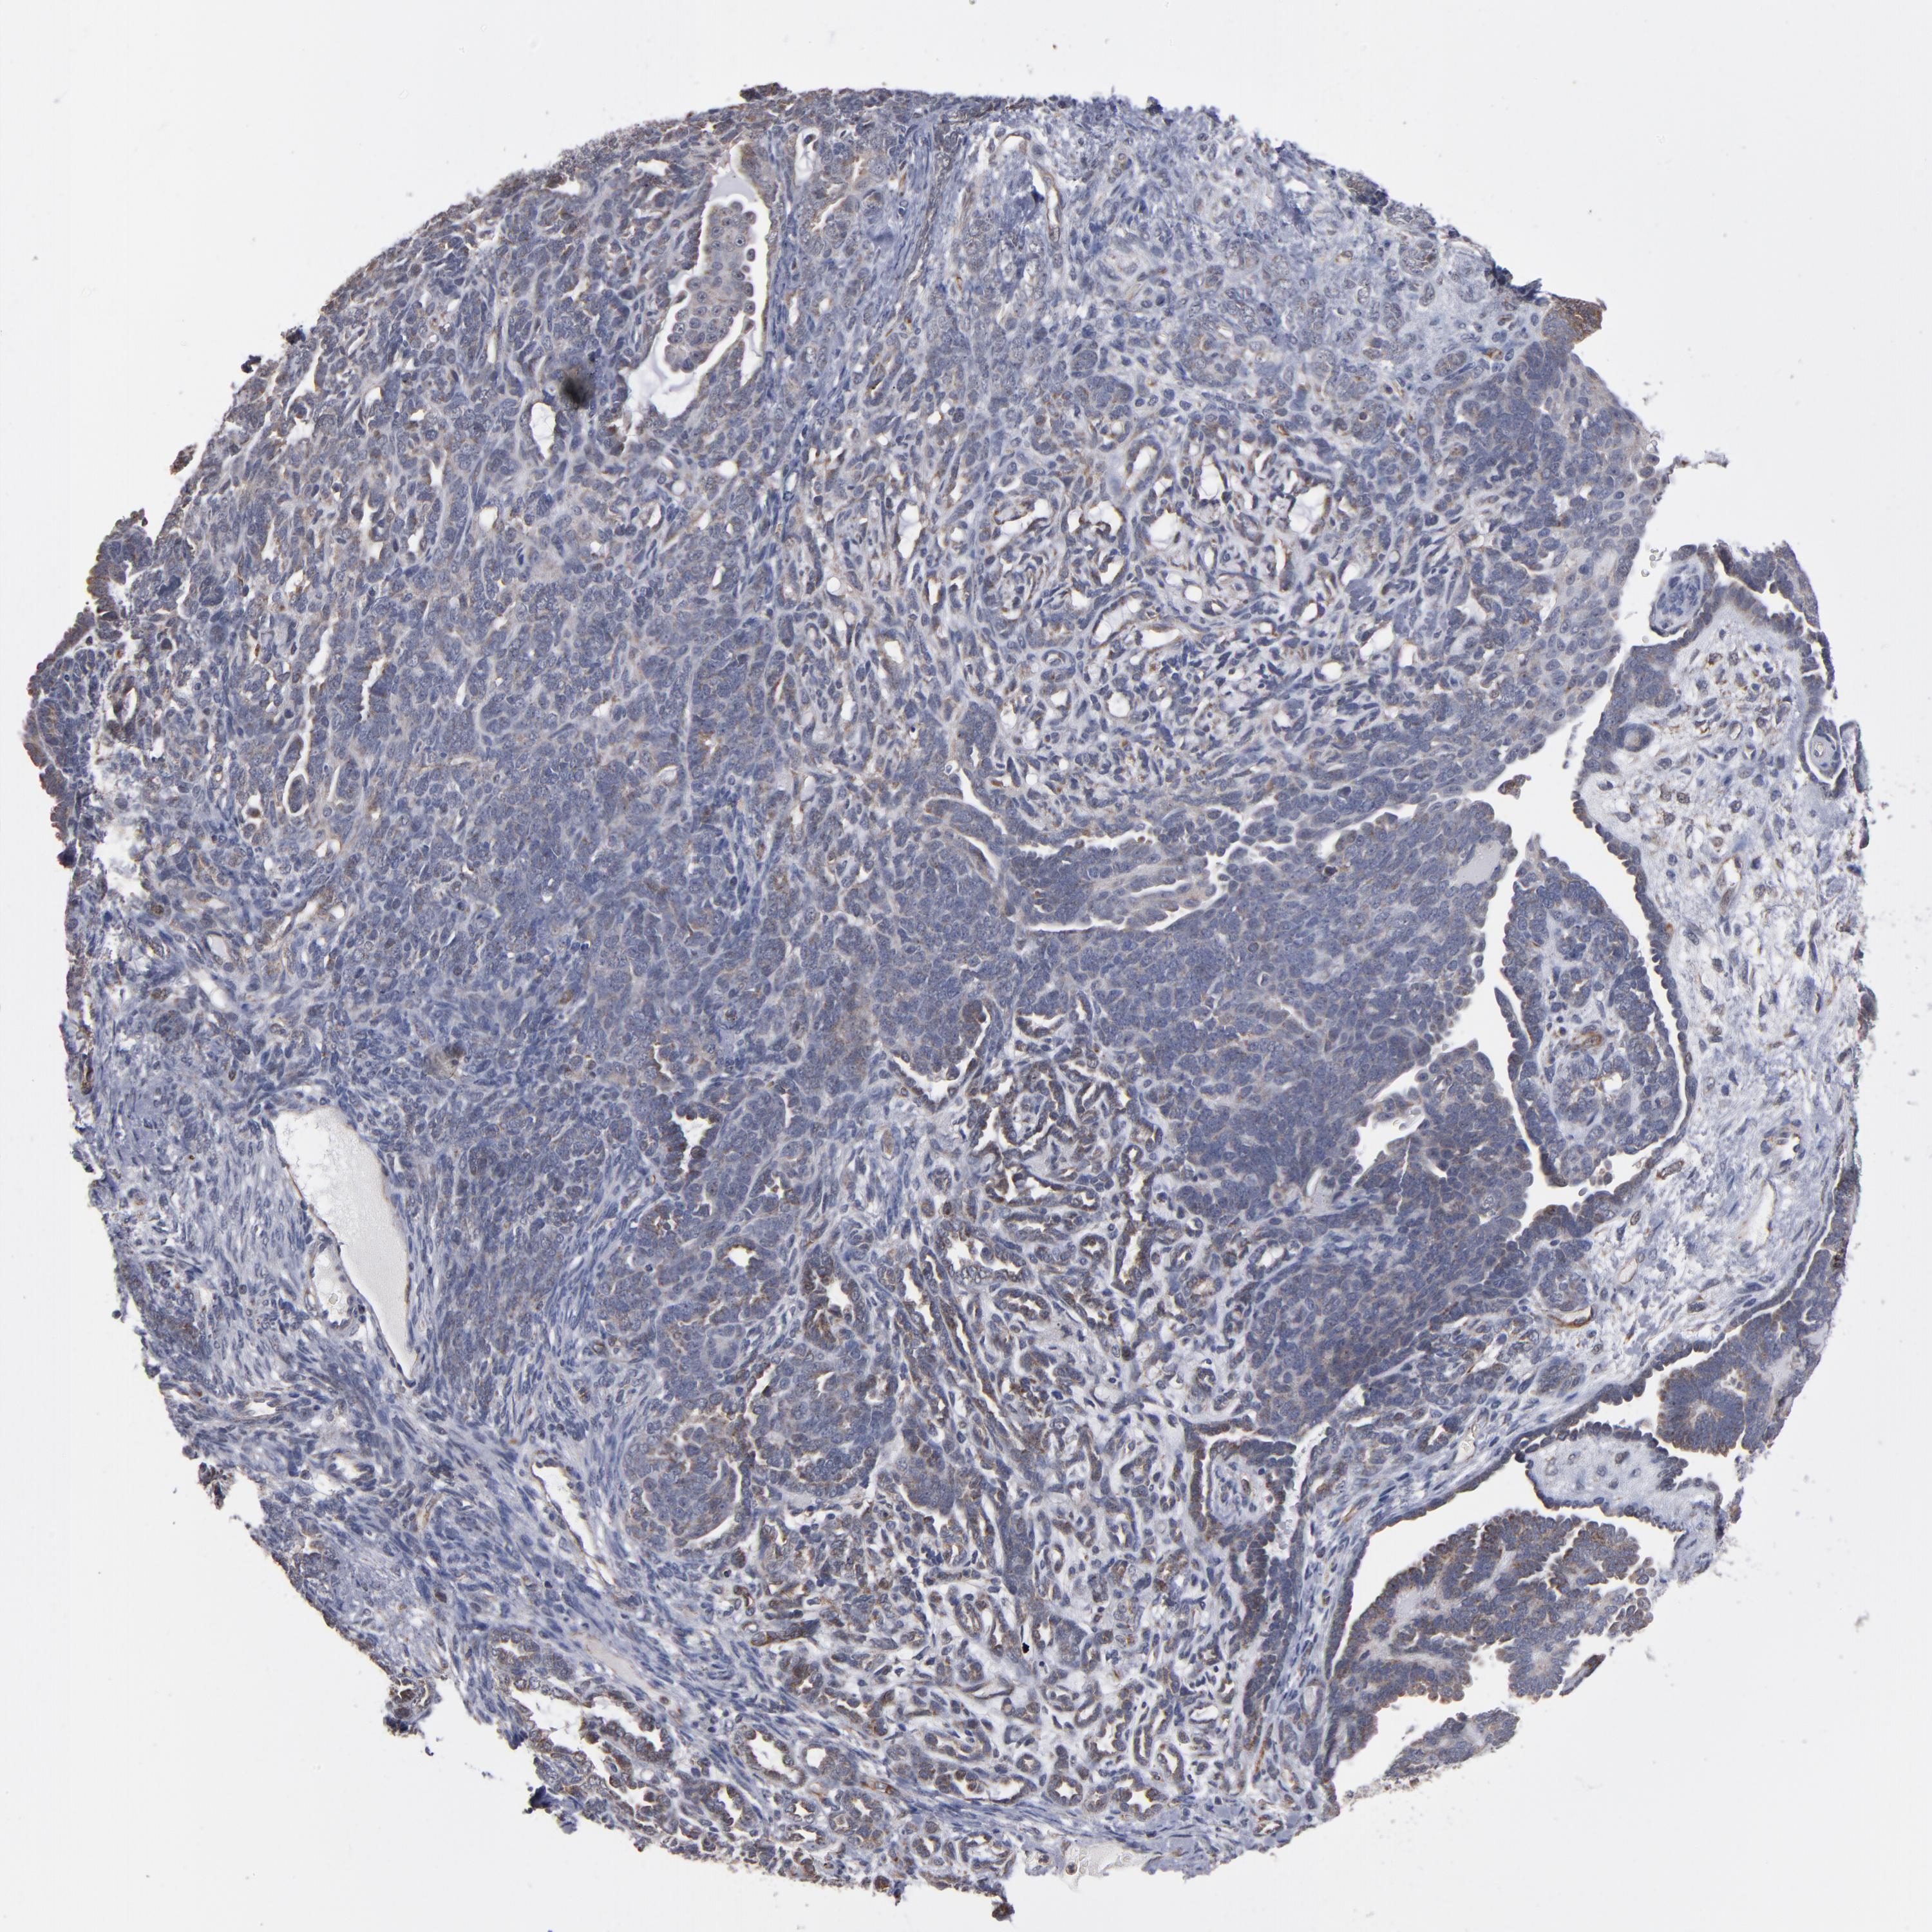

ENDOMETRIAL CANCER - Protein expressioni

A mouse-over function shows sample information and annotation data. Click on an image to view it in a full screen mode. Samples can be filtered based on level of antibody staining by selecting one or several of the following categories: high, medium, low and not detected. The assay and annotation is described here.

Note that samples used for immunohistochemistry by the Human Protein Atlas do not correspond to samples in the TCGA dataset.

Antibody stainingi

Antibody staining in the annotated cell types in the current human tissue is reported as not detected, low, medium, or high, based on conventional immunohistochemistry profiling in selected tissues. This score is based on the combination of the staining intensity and fraction of stained cells.

Each image is clickable and will lead to virtual microscopy that enables deeper exploration of all samples and also displays staining intensity scores, fraction scores and subcellular localization as well as patient and tissue information for each sample.

Antibody HPA002893

Staining

High

Medium

Low

Not detected

Intensity

Strong

Moderate

Weak

Negative

Quantity

>75%

75%-25%

<25%

None

Location

Nuclear

Cytoplasmic/membranous

Cytoplasmic/membranous,nuclear

Adenocarcinoma, NOS

Neoplasm, malignant, NOS